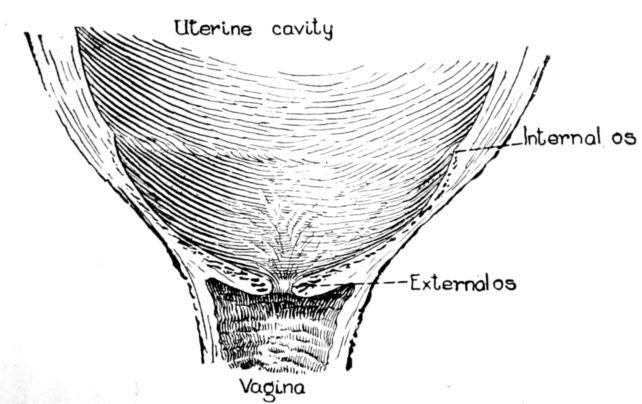

| xxi63, 64, 65, 66. | Diagrams showing stages of dilatation and obliteration of cervix | 234 |

The uterus as a whole is comprised of three parts: the fundus, that firm, rounded, head-like part above; the body, or middle portion, and the cervix, or neck, below. It is in the body and cervix that we find the long, narrow uterine cavity, divided by a constriction into two parts. The cavity of the body is little more than a vertical slit, being so flattened from before backward 33that the anterior and posterior surfaces are nearly if not quite in apposition. It is somewhat triangular in shape with an opening at each angle. (Fig. 11.) The lower of these openings leads into the cavity of the cervix through a constriction termed the internal os, while at the cornua, or two upper angles, are the openings into the Fallopian tubes.

The cavity of the cervix is spindle-shaped, being expanded between its two constricted openings, the internal os above and the external os below, which opens into the vagina. The external os in the virgin is a small round hole but has a ragged outline in women who have borne children.